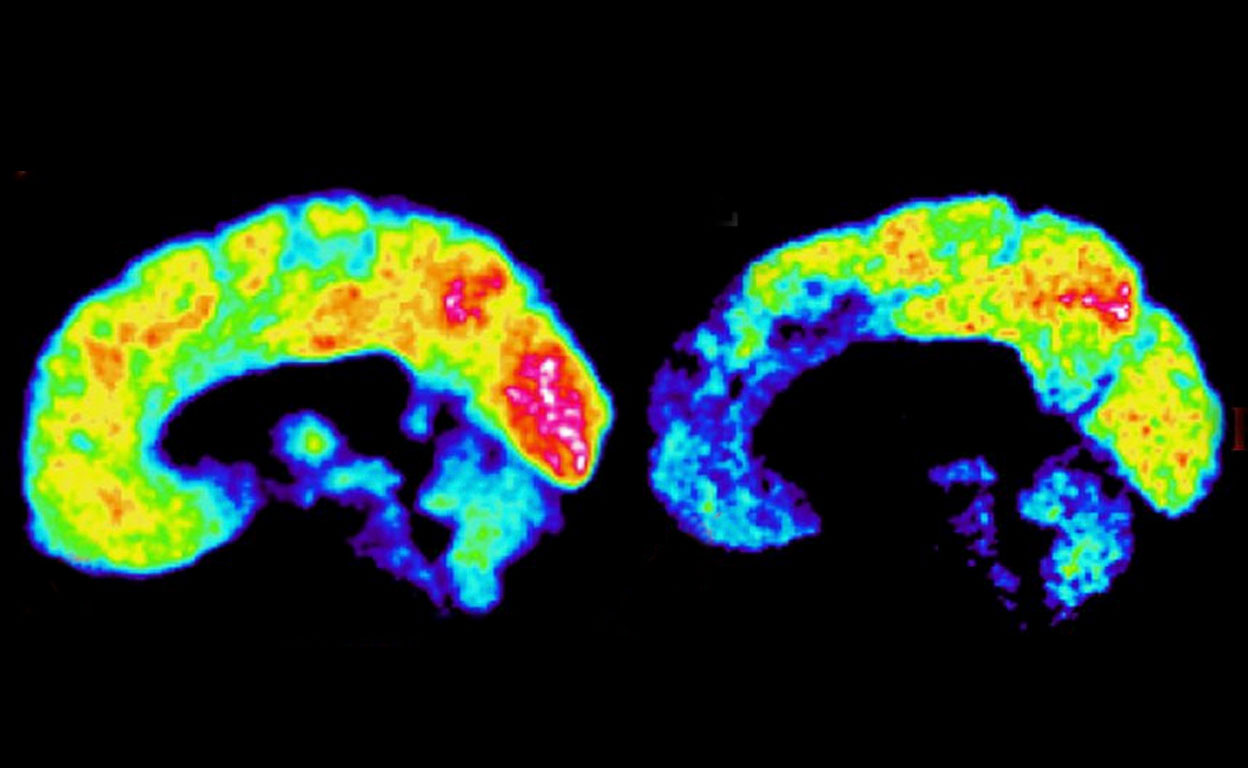

Tras reunir toda la información disponible sobre Vladímir Putin, el neurocientífico norteamericano James Fallon —profesor de Psiquiatría, Anatomía y Neurobiología de la Universidad de California— ha desarrollado la que, según él, sería una neuroimagen del cerebro del presidente de Rusia. Para explicarla mejor, Fallon —que lleva años estudiando el cerebro de los dictadores de Corea del Norte, Cuba, Bielorrusia, Venezuela y, sobre todo, Rusia— ha señalado en azul las áreas con baja actividad cerebral y en rojo, las áreas con actividad por encima de lo normal. Nos lo explica.

En todos los psicópatas esta amplia área (cortezas orbital y cingulada anterior, lóbulo frontal, amígdala…) presenta baja actividad. Es una zona que se activa pronto en el niño… si no sufre un trauma temprano. Se trastocan así los rasgos básicos de la personalidad, la conducta social y moral, el sentimiento de culpa, los impulsos agresivos, la valoración del riesgo…